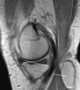

Idiopathic popliteal cyst